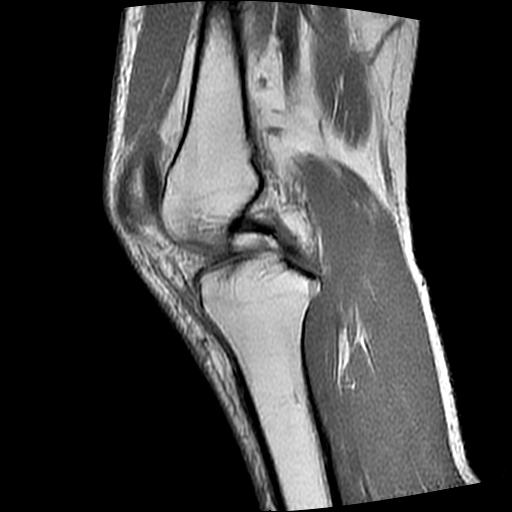

标题: MRI1265:男性40岁,右膝关节 [打印本页]

标题: MRI1265:男性40岁,右膝关节

40岁男性,右膝关节外伤,x光平片示,髁间隆突撕脱骨折。

1、前交叉韧带撕裂;

2、外侧半月板后角撕裂;

3、关节腔积液。

前交叉韧带撕裂,关节腔积液.

半月板1-2级损伤   前交叉韧带撕裂伤   关节腔少量积液  诸骨未见新鲜外伤性改变

髁间隆突撕脱骨折;内侧副韧带损伤。

内侧副韧带撕裂及关节腔积液是肯定的,但是前交叉撕裂确定吗?会不会有容积效应的因素,因为前一张前交叉显示清楚,连续性良好,且较光滑。请问楼主有关节镜支持吗?我们医院也经常有这样的患者,但苦于没有关节镜,而无法对照、证实(除非完全断裂),出现了不同的诊断结果只能毫无意义的争论。

1、前交叉韧、内侧副韧带撕裂;

3、关节腔积液。4、髁间脊撕脱骨折。

除了关节积液外并无韧带撕裂,acl胫侧附着点有2束,正常情况下脂肪信号。此病例应加做压脂像以便观察是否有骨损伤。